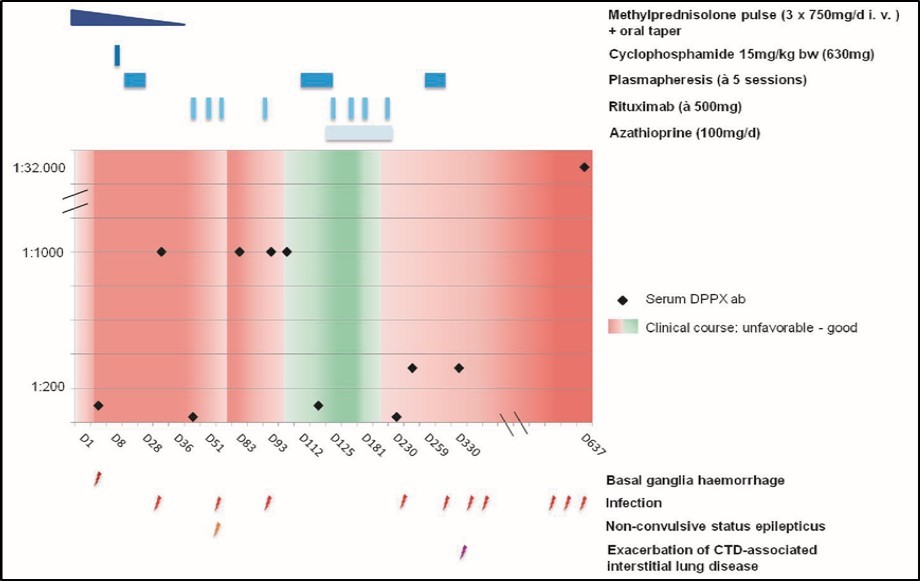

Owing to the uncommon clinical presentation of cerebral vasculitis we screened for antineuronal-autoantibodies. Anti-DPPX-antibodies were detected in CSF and serum (both 1:100, cell-based indirect immunofluorescence assay) establishing the additional diagnosis of anti-DPPX-encephalitis. Whole body FDG-PET/CT did not suggest underlying malignancy. After cyclophosphamide and plasmapheresis the FLAIR-hyperintense lesions on MRI disappeared almost completely and MRA still showed normalization of intracranial arteries (Figure 1D). Anti-DPPX-titer dropped to 1:32. Hyperekplexia and myoclonus decreased under symptomatic treatment with clonazepame. Therapy with rituximab was started. After two months she was transferred to a rehabilitation unit from where she returned three weeks later somnolent, tetraplegic and anarthric. EEG revealed non-convulsive status epilepticus that was successfully terminated by valproate, also leading to some clinical improvement. However, as anti-DPPX-titer had risen to 1:1000 we initiated a second plasmapheresis-cycle. Thereafter anti-DPPX-titer dropped to 1:100. Another cycle of rituximab and treatment with azathioprine were started. Five weeks later she was again transferred to the rehabilitation unit, where she improved markedly, being able to use a wheelchair independently, walk over short distances in a gait training device, use her right arm and ingest food orally.

Four months after initiation, azathioprine was stopped due to leuko- and thrombocytopenia. One month later, myoclonus increased, her cognition deteriorated, and she developed infectious complications requiring readmission to our hospital. Cerebral MRI including MRA showed timely resorption of basal ganglia hemorrhage without any further pathologies. Anti-DPPX-titer had risen to 1:320. Since FACS-analysis showed complete peripheral depletion of B-lymphocytes we only conducted a third plasmapheresis-cycle.

Thereafter she developed pneumonia with sepsis and respiratory failure requiring mechanical ventilation. Thoracic CT and echocardiography suggested exacerbation of slightly preexisting, CTD-associated pulmonary fibrosis and pulmonary hypertension causing congestive heart failure. Tracheotomy became necessary. After successful weaning from mechanical ventilation right heart catheterization confirmed severe pulmonary hypertension (PA pressure ~80 mmHg) along with right heart failure. A therapy with Macitentan and Tadalafil was started. Blocked tracheostomy was kept in place to prevent aspiration due to dysphagia and CTD-associated disturbance of gastrointestinal motility. Nutrition was maintained via the PEG feeding tube. Communication was realized non-verbally and via a communication board. In addition to the left-sided hemiparesis limb contractures limited the patient's mobility. Altogether the patient was functionally completely dependent and predominantly bedridden.

During early neurological rehabilitation pulseless ventricular tachycardia required cardiopulmonary resuscitation. Multiple infectious complications, especially concerning the lungs and urinary tract, deteriorated the patient's condition even more so when she returned back home she required 24-hour intensive care by a nurse.

21 months after initial contact, the patient was admitted to our hospital's internal medicine unit because of an acute renal failure with urosepsis requiring hemodialysis. In addition cardiac cirrhosis with ascites was diagnosed. In the neurological examination the patient was somnolent, showed a spastic, left-sided hemiparesis and a newly increase of myclonus. Cerebral MRI displayed blood degradation products in the right frontal subarachnoid space, a new microbleed in the left temporal white matter as well as whole brain atrophy (Figure 1E). Anti-DPPX-titer had risen to 1:32000. In the further course, the patient developed aspiration pneumonia eventually causing septic shock with multiple organ failure that lead to her death at the age of 34. An autopsy was not performed (Figure 2).

Figure 2.Overview of disease course. 21 months follow-up of antibody (ab) titers in serum in parallel with immunosuppressive/immunomodulatory interventions and specific clinical events as indicated. The clinical course is represented by different colors from dark red (unfavorable) to dark green (good).